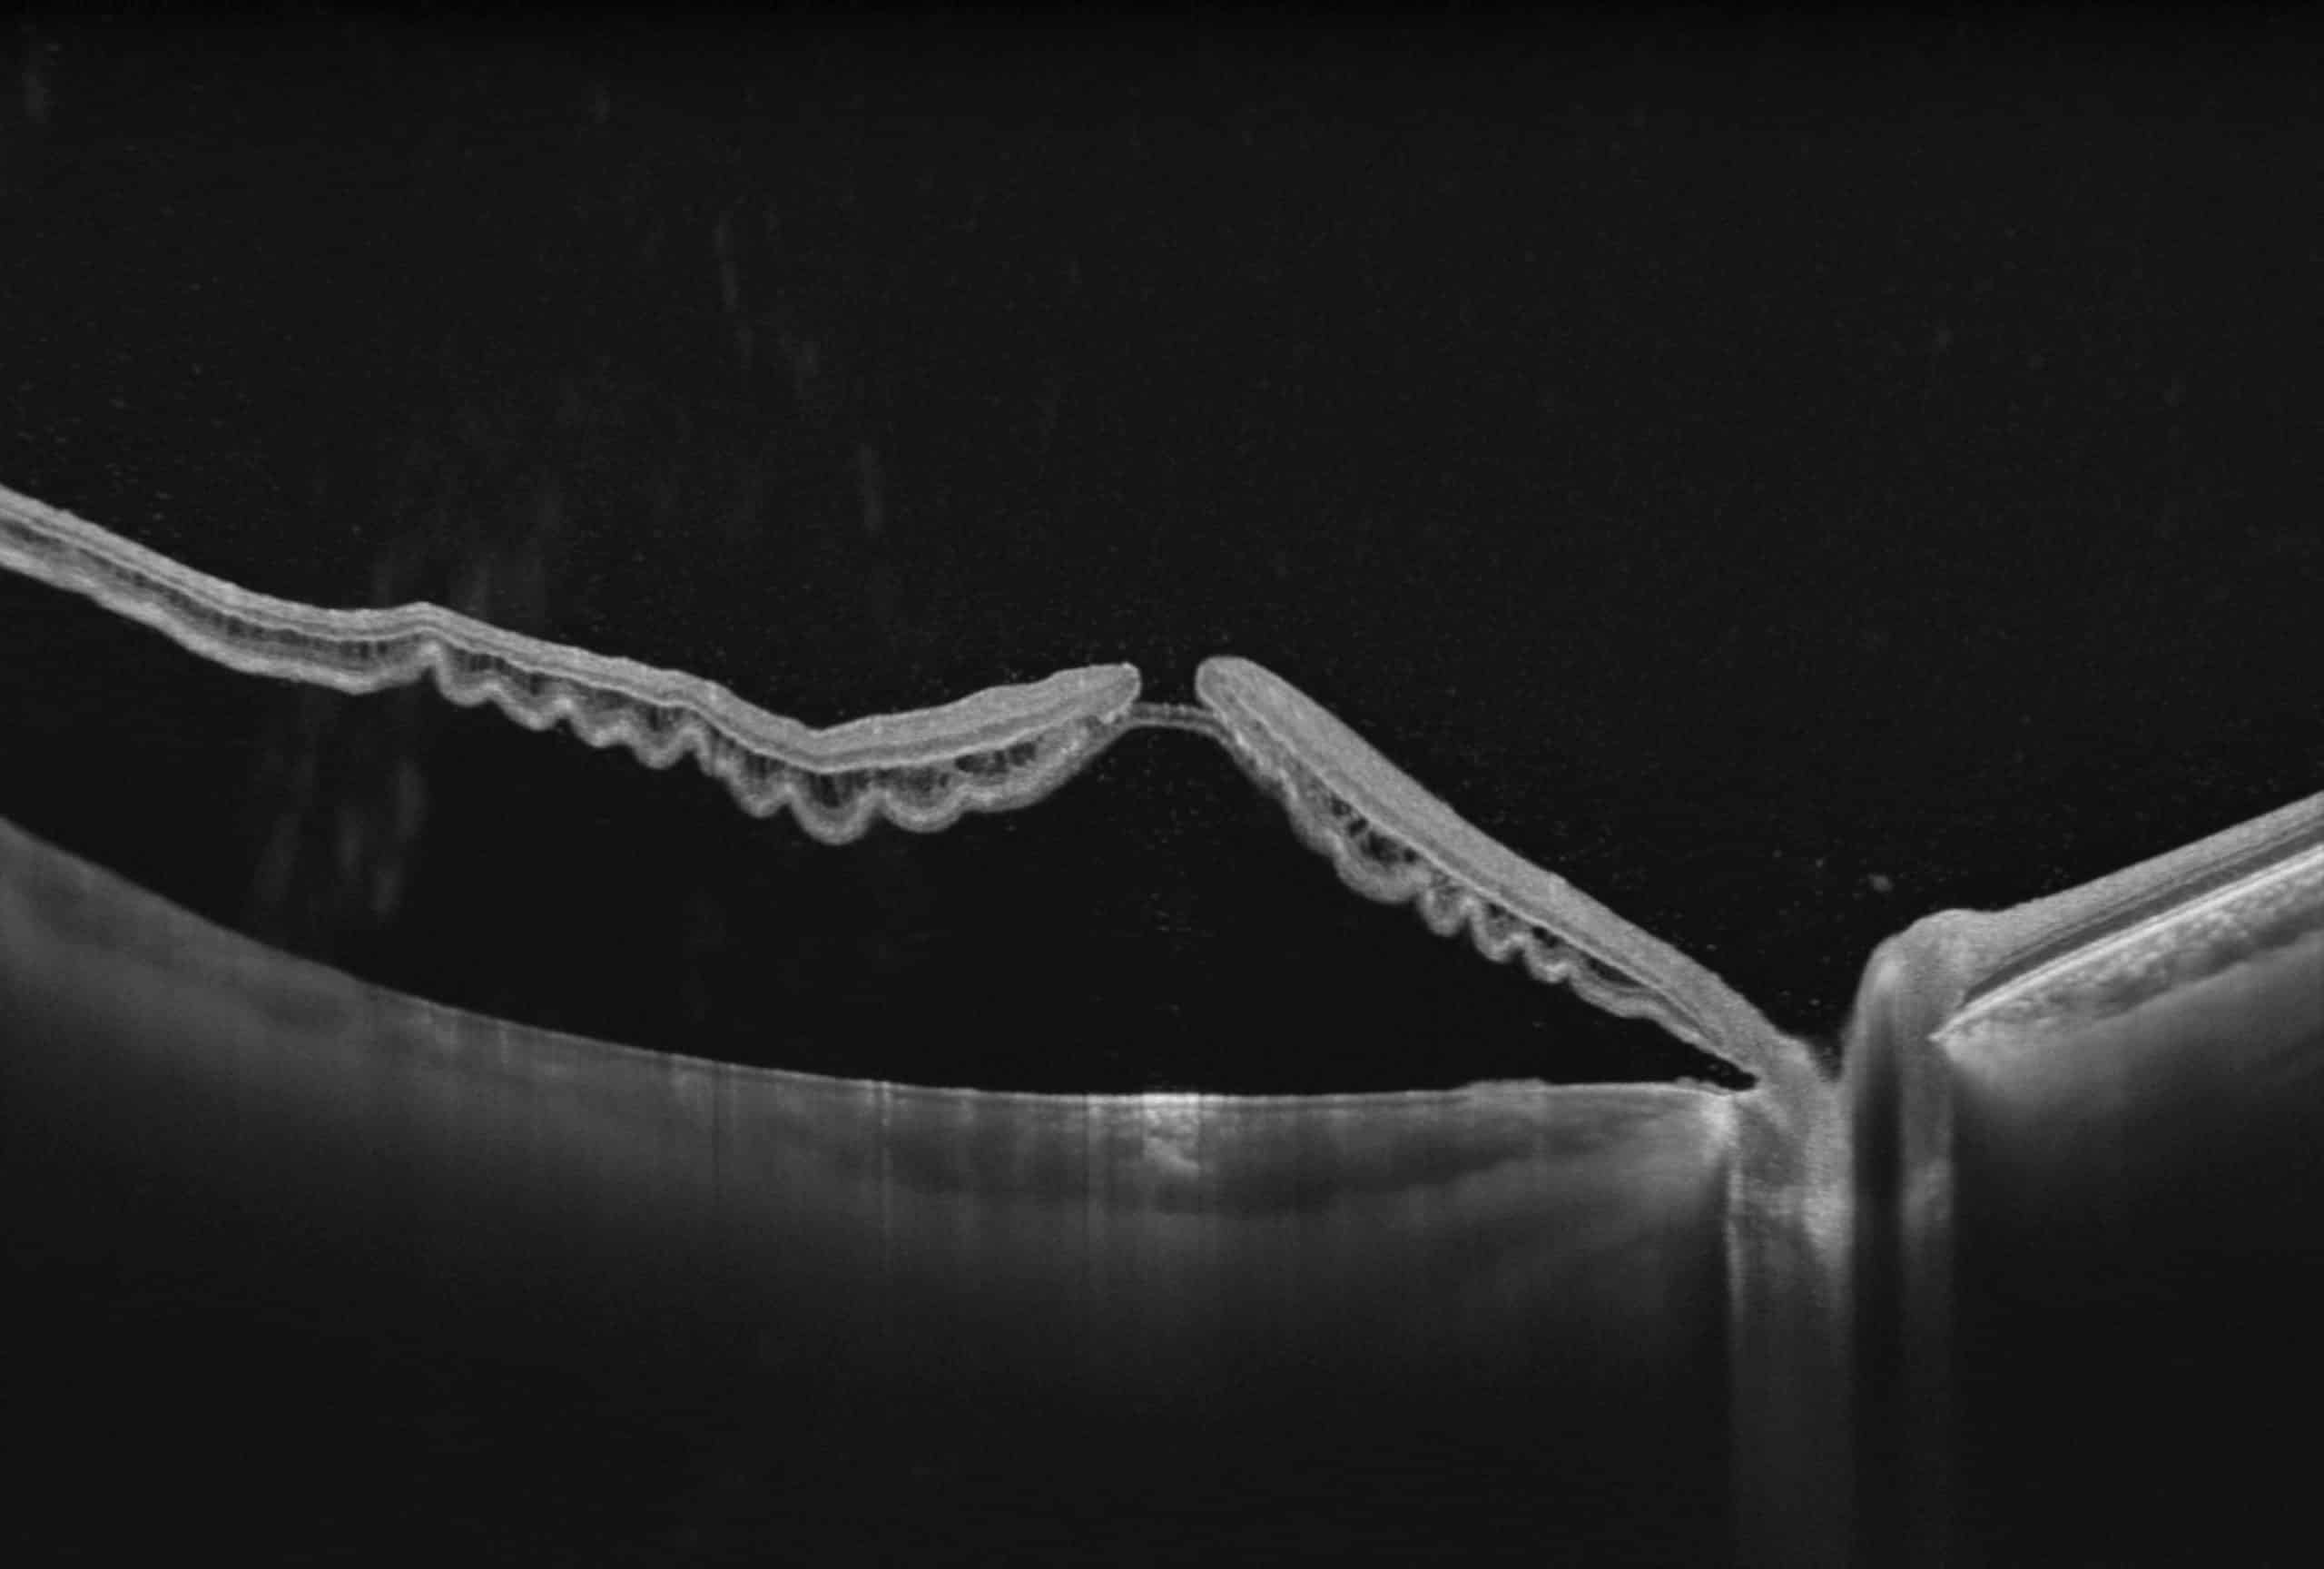

100kHz speed full-range swept-source OCT for anterior and posterior

- HD Anterior Scan with Anterior OCTA

- 15mm Scan depth anterior